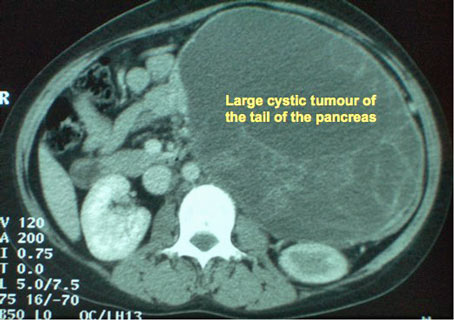

CT scan showing a large cystic tumour arising from the pancreatic tail in a young woman

Solid pseudopapillary tumour is a rare, slowly-progressive but malignant tumour, seen in women in the child-bearing age, and manifests as a large, part-solid, part-cystic tumour. The term Cystadenocarcinoma is often used to describe an adenocarcinoma (see below) that has partly liquefied at its centre.